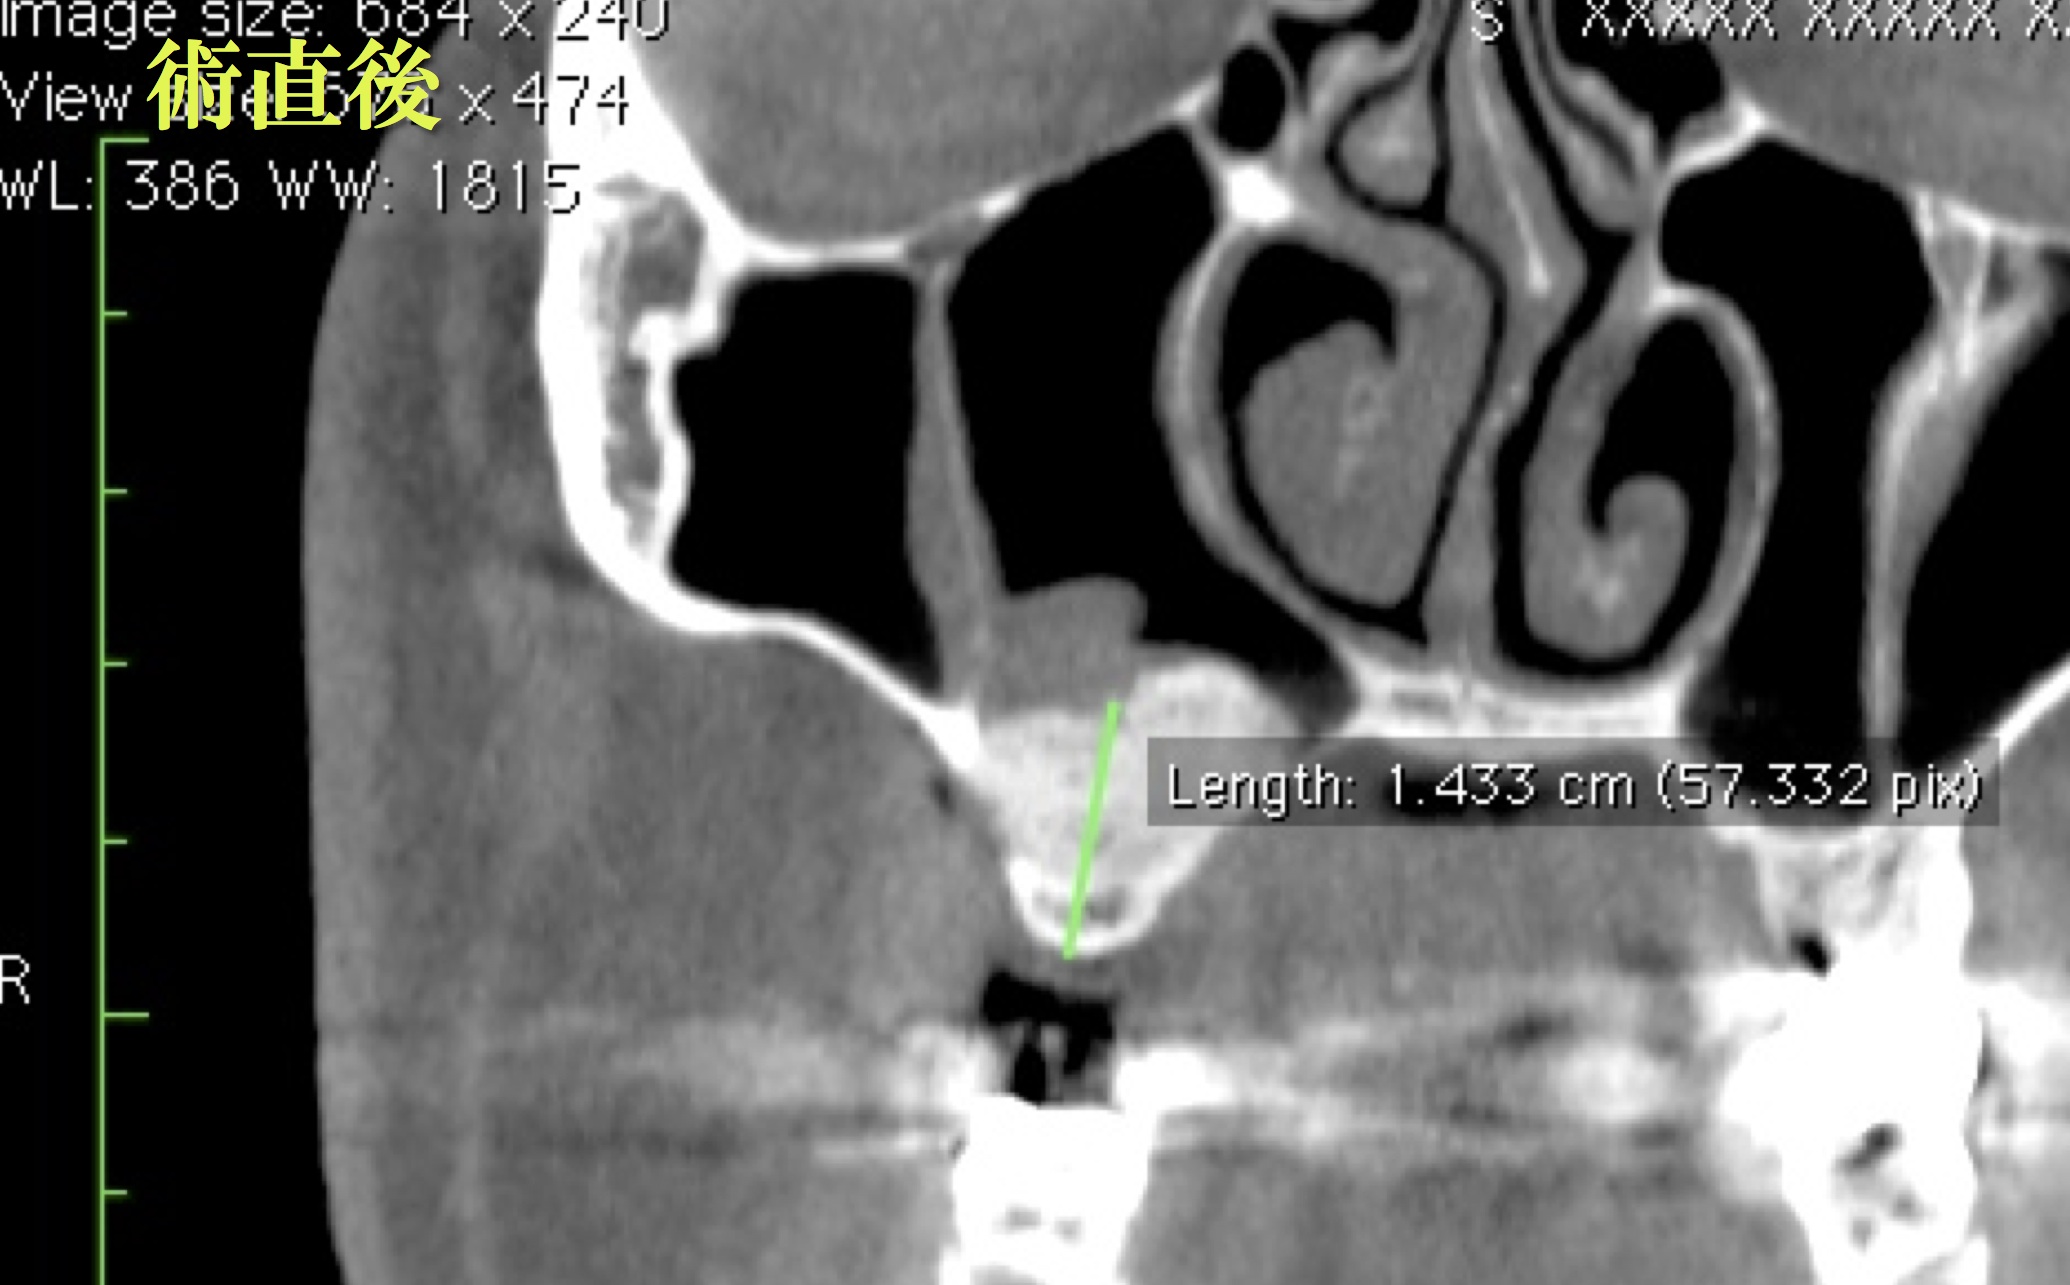

上顎洞底挙上術に関する専門的な解説書。絶版希少本- タイトル: Perfect Sinus Lift- 著者: 小林 文夫, 高橋 亮男- 出版社: ゼニス出版- 内容: 上顎洞底挙上術に関する詳細な解説- ISBN: 9784897260313裁断してません。ご覧いただきありがとうございます。